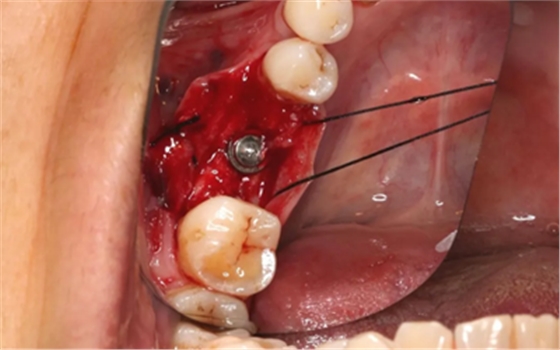

13、术后4个月复查、植骨

4月后二期手术前口内情况

(摄于2017年8月10日)

翻瓣,发现种植体唇侧骨壁吸收至根部。

远中骨壁部分吸收,近中及舌侧骨壁完整,种植体无松动。